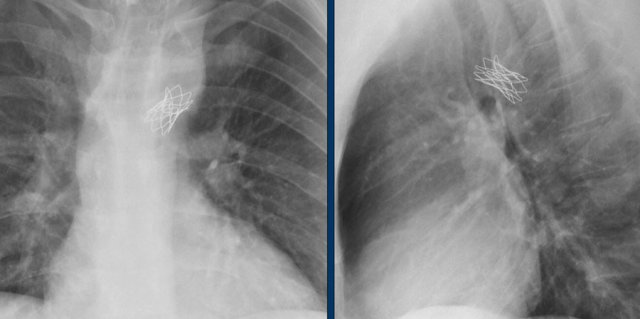

Here a lateral view of a child with an ASD and an Amplatz closure device.

A lateral view of a child with an ASD and an Umbrella Rashkind closure device.

Images of a patient with an ASD and an Amplatz closure device.